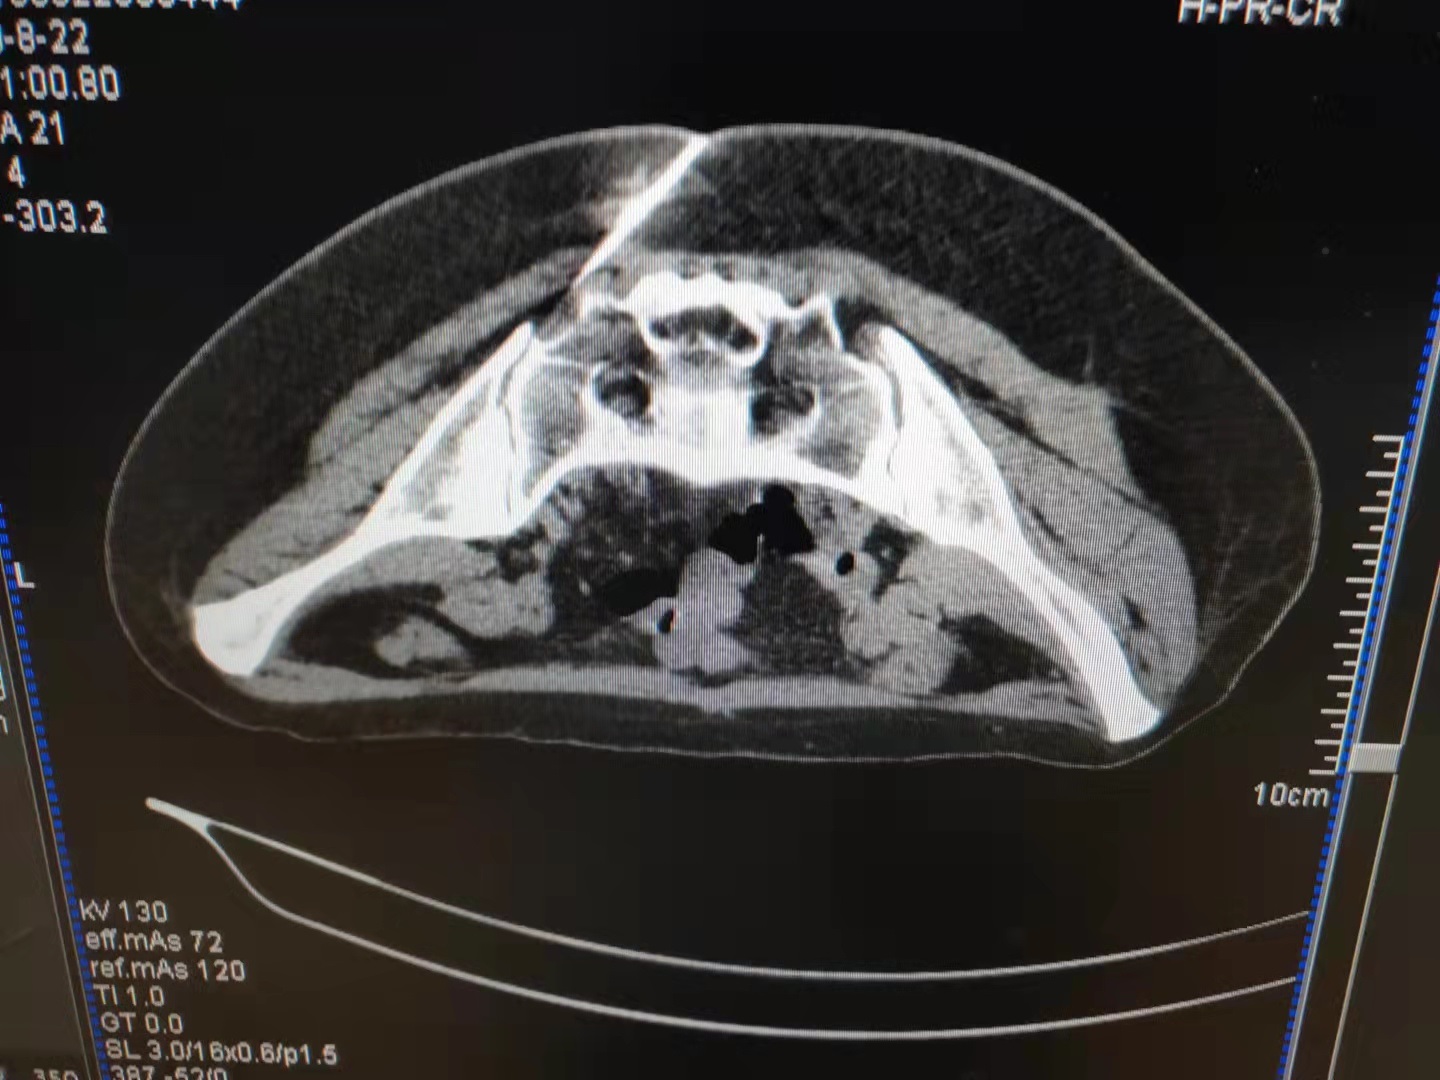

骶髂关节炎多为急性发作,由运动、劳累或者分娩导致,疼痛明显,对疼痛科医师的诊断能力是很大的考验。这是我院疼痛科明确诊断后在CT引导下一例精准的骶髂关节治疗,治疗后当日患者便能下地走路。

顽固性会阴痛难以启齿却困扰着很多病友,这是一例CT引导下精准化奇神经毁损治疗顽固性会阴痛,治疗后第二日便收获了病友大大的赞。